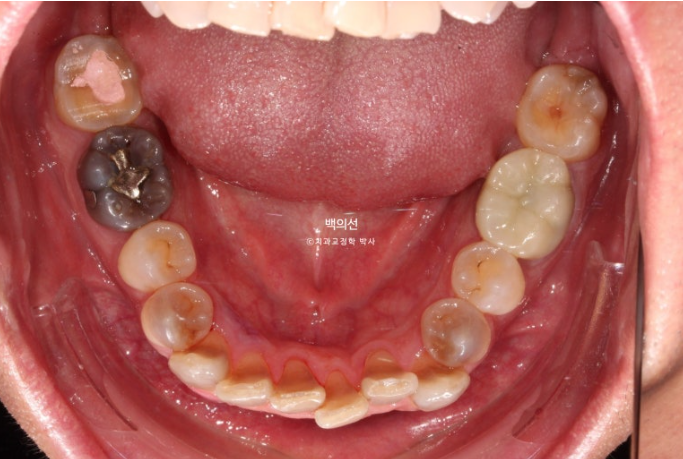

In the lower front teeth, there are varying heights in addition to the canine crowding.

The lower front teeth have stricter conditions for no-prep laminate than the upper front teeth.

Because the laminate has to wrap around the incisal edge of the lower front teeth, there needs to be some distance between the upper front teeth and the lower front teeth.

The canine crowding is fairly severe.